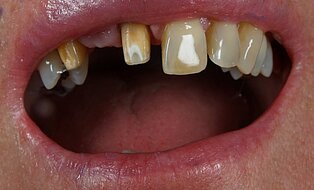

Vom Langzeitprovisorium zur TEK 1 Arbeit